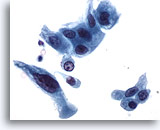

Figure 32Catheterized urine, high grade urothelial carcinoma

Cells of high grade urothelial carcinoma have high N/C ratios. 40x

Cells of high grade urothelial carcinoma have high N/C ratios. 40x

Figure 32

Catheterized urine, high grade urothelial carcinoma

Cells of high grade urothelial carcinoma have high N/C ratios.

40x

Catheterized urine, high grade urothelial carcinoma

Cells of high grade urothelial carcinoma have high N/C ratios.

40x